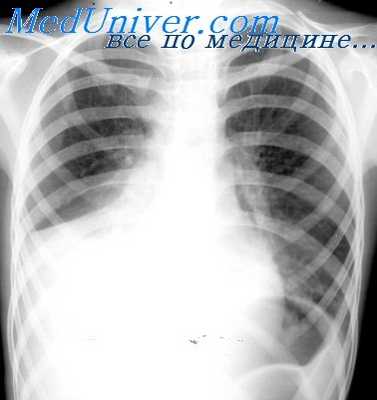

- Рентген. Полипозиционная рентгенография и рентгеноскопия легких при эмпиеме плевры обнаруживают интенсивное затенение. Для уточнения размеров, формы осумкованной эмпиемы плевры, наличия свищей выполняют плеврографию с введением водорастворимого контраста в плевральную полость. Для исключения деструктивных процессов в легких показано проведение КТ, МРТ легких.

Наряду с клиническими проявлениями экссудативного плеврита при осмотре пациента выявляется асимметрия грудной клетки, выбухание межреберных промежутков на соответствующей половине грудной клетки, отставание пораженной стороны при дыхании. Перкуторный звук над экссудатом притуплен, бронхофония и голосовое дрожание ослаблены, дыхание слабое или не выслушивается. Верхняя граница выпота определяется перкуторно, при рентгенографии легких или при помощи УЗИ плевральной полости.